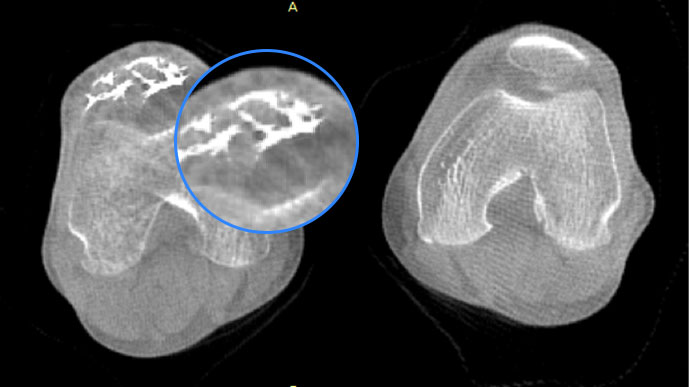

膝关节

关闭金属伪影校正

开启金属伪影校正